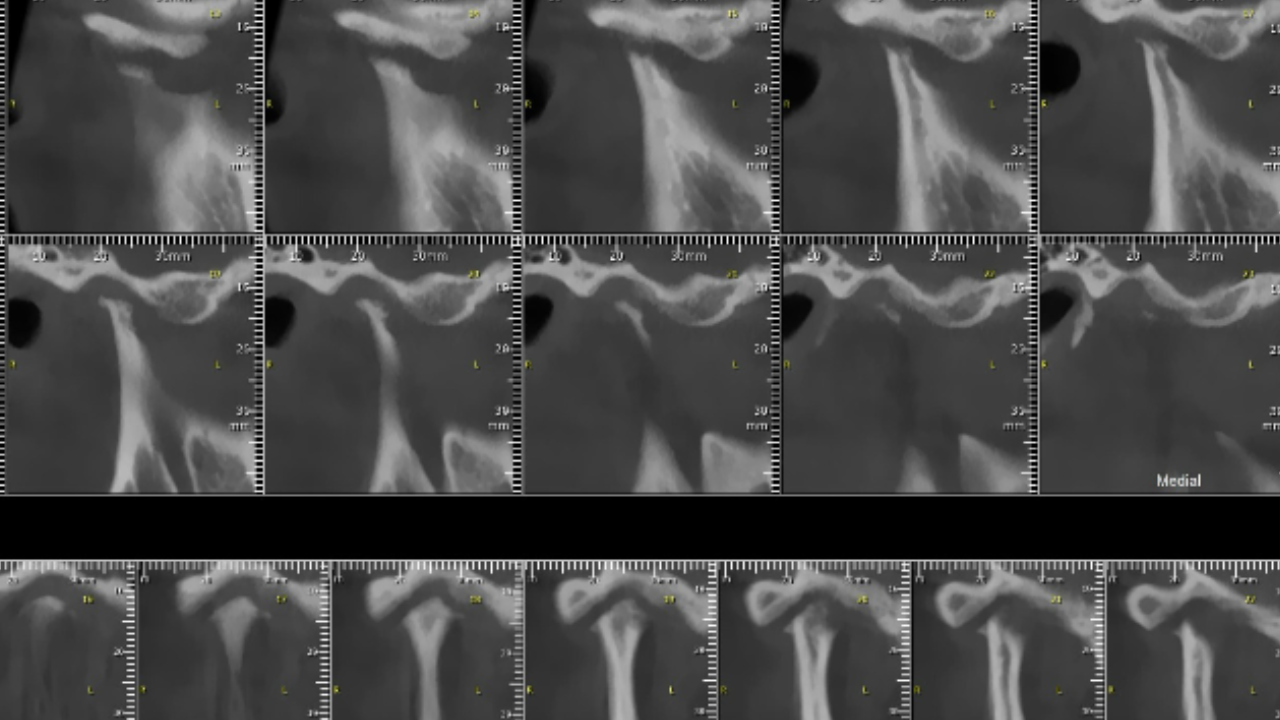

El tratamiento dependerá de la necesidad de cada caso. Un tratamiento exitoso necesita una base diagnóstica sólida apoyada en imágenes complementarias cuando lo necesite.